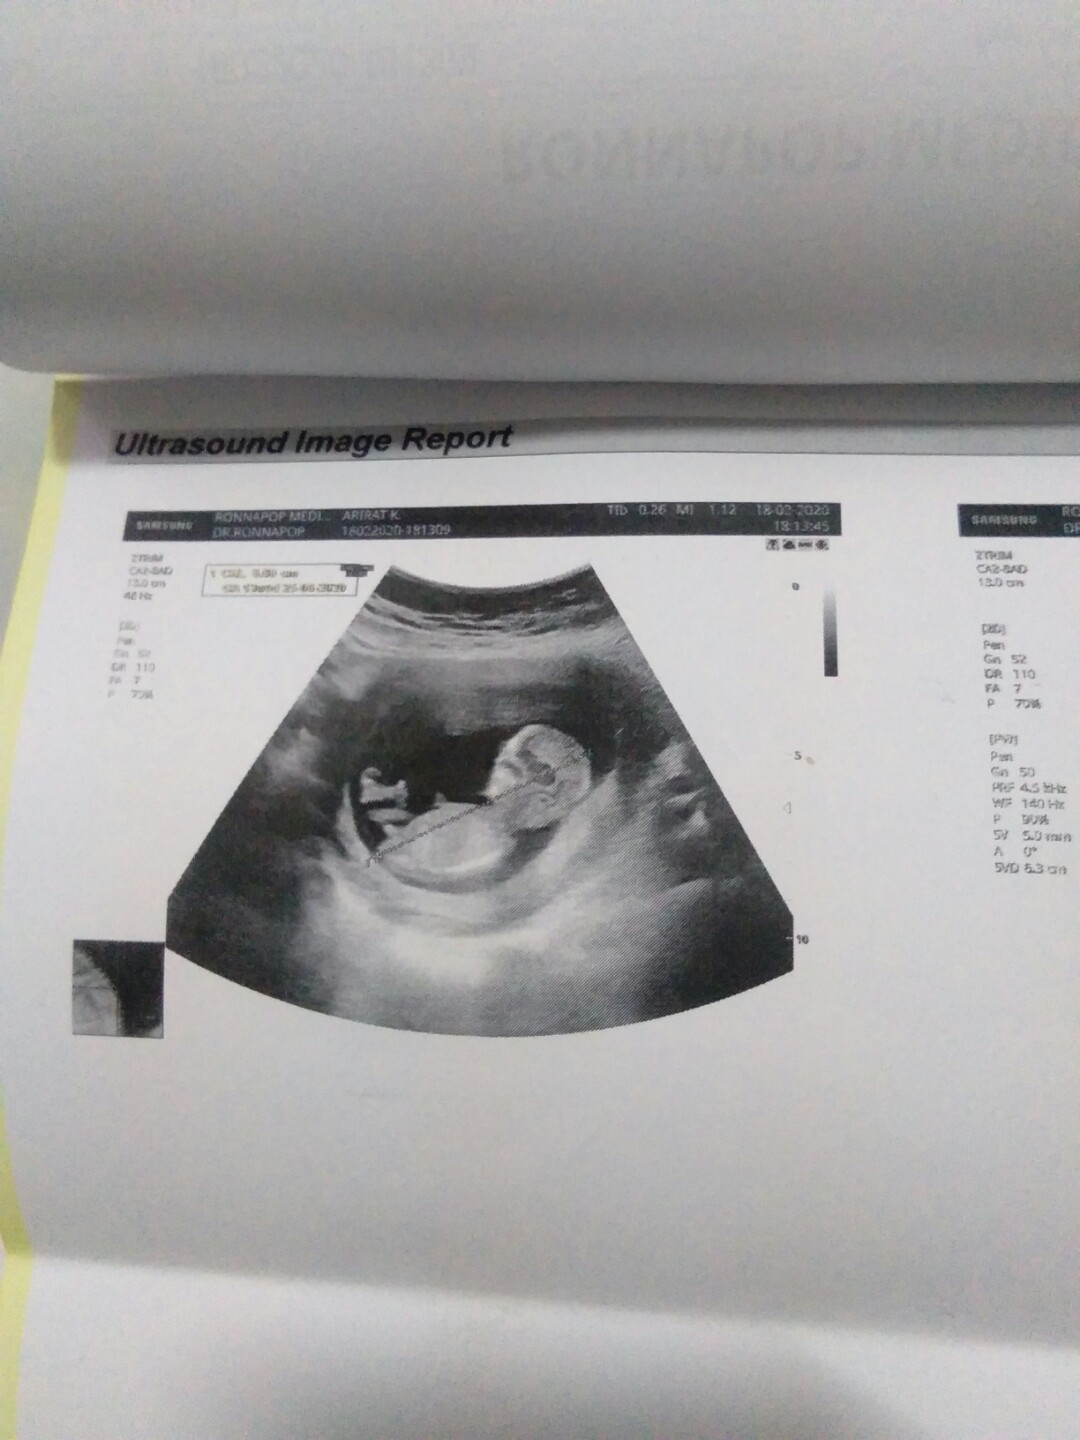

11วีคค่ะ

11w5dค่ะ